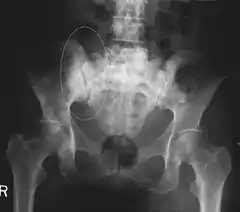

Skeletal Radiography

A plain film x-ray of the entire body can identify bone metastasis. However, the sclerotic or osteolytic lesions must be at least 1 cm in diameter.[14] A combination of X-ray, CT and MRI scans may be most sensitive in the diagnosis of cancerous bone metastasis.[14]